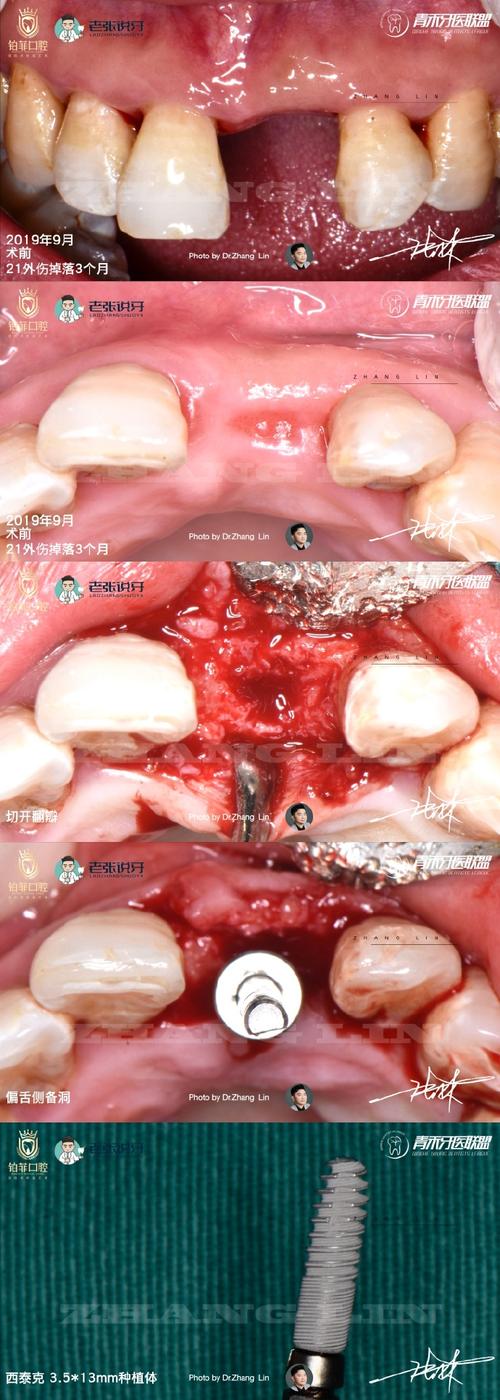

| 手术操作因素 | 切口类型与大小 | 微创切口(如种植导板引导的小切口)创伤小,恢复快;传统翻瓣切口创伤大,愈合时间延长。 |